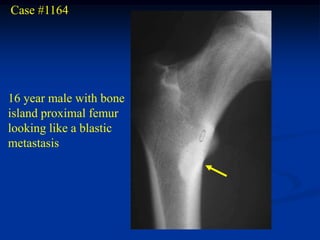

Case #1164

16 year male with bone

island proximal femur

looking like a blastic

metastasis

CTscan

Coronal T-2 MRI

Axial T-2 MRI

Macro section of resected bone island specimen